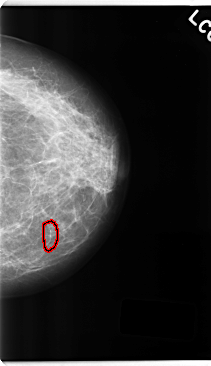

C_0239_1.LEFT_CC

LEFT_CC LINES 4752 PIXELS_PER_LINE 2736 BITS_PER_PIXEL 12 RESOLUTION 50 OVERLAY

FILE: C_0239_1.LEFT_CC.OVERLAY

TOTAL_ABNORMALITIES 1

ABNORMALITY 1

LESION_TYPE CALCIFICATION TYPE FINE_LINEAR_BRANCHING DISTRIBUTION LINEAR

ASSESSMENT 4

SUBTLETY 5

PATHOLOGY BENIGN

TOTAL_OUTLINES 1

BOUNDARY